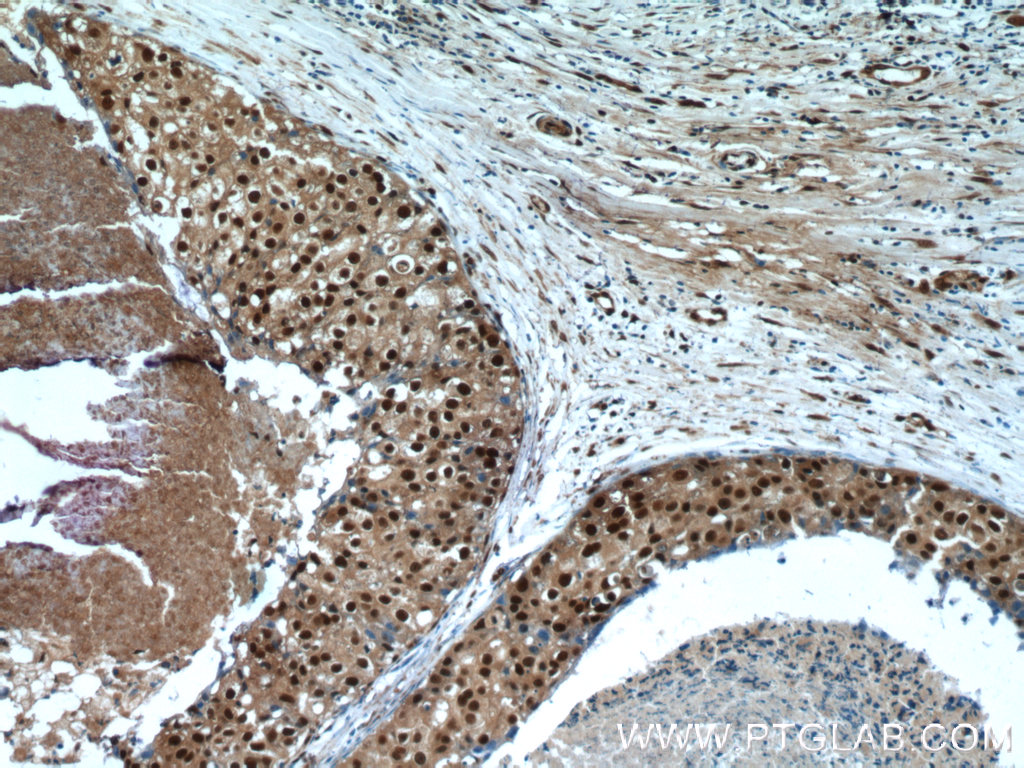

| Positive IHC detected in | human breast cancer tissue, mouse testis tissue Note: suggested antigen retrieval with TE buffer pH 9.0; (*) Alternatively, antigen retrieval may be performed with citrate buffer pH 6.0 |

| Immunohistochemistry (IHC) | IHC : 1:20-1:200 |

Steroid receptor RNA activator 1 (SRA1), also known as seroid receptor RNA activator protein (SRAP) or SRA, is involved in modulating the activity of multiple transcription factors including the estrogen receptor (ER) (PMID: 20398657). It may play a role in tumorigenesis (PMID: 16152589). The SRA1 gene encodes both SRA1 protein and a non-coding functional RNA that functions as part of a ribonucleoprotein complex activating steroid receptor induced transcription. This polyclonal antibody recognizes endogenous SRA1 isoforms which migrate as a doublet on SDS-PAGE gels (PMID: 12565891; 23907597).